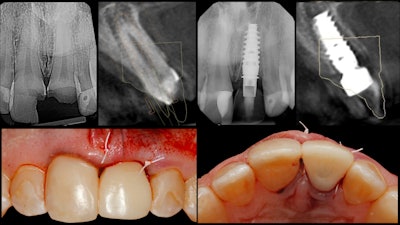

After a six-month period to allow the patient's soft tissue to heal and the implant to integrate, the patient returned to the office for re-evaluation. At that point, the original provisional design was modified to full-emergence contours, brought into occlusion, and modified from a screw-retained restoration into a split design with a separate IPS e.max CAD (Ivoclar Vivadent) custom abutment and an abutment-supported implant crown.

The restorative components were then milled on the MCXL, crystallized in a Programat P500 furnace (Ivoclar Vivadent), and characterized using stain and glaze. The abutment was then bonded onto a TiBase (Dentsply Sirona) (figure 6).

Finally, tooth #8 was prepared for a crown restoration. The tooth was imaged, and the crown was designed and milled so that both restorations could be delivered simultaneously to complete the entire surgical and restorative process in only two clinical visits (figure 7).

By starting the treatment-planning process with the end result in mind, the entire digital implant workflow was predictably navigated, and an excellent clinical result was achieved. Furthermore, both the patient's and the clinician's chair time can be reduced through utilization of integrated digital processes of CBCT and CAD/CAM technology.